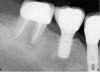

Figure 11  The mandibular first molar was fractured. Note the periapical lesions around this tooth.

Figure 11

Figure 12  After the first molar was extracted and hemisected without damaging the interradicular bone, an initial osteotomy was prepared in the interradicular bone utilizing a 2.2-mm-wide bur.

Figure 12

Figure 13  A radiograph of a guide pin in the prepared osteotomy.

Figure 13

Figure 14  An implant with a 4.8-mm-wide body and a 6.5-mm-wide restorative platform was placed in the interradicular bone following appropriate preparation.

Figure 14

Figure 15  Another view of the implant in the interradicular bone. Note that the mesial and distal aspects of the interradicular septum have been lost. The implant attained primary stability from the buccal and lingual aspects of the interradicular bone.

Figure 15

Figure 16  A radiograph of the restored implant taken after more than 7 years in function demonstrates stable peri-implant crestal bone levels.

Figure 16